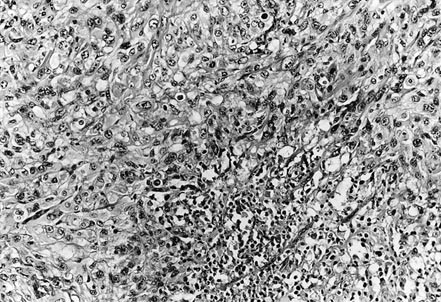

Histologically, 12 tumors (60%) were classified as the large-cell subtype, 6 (30%) as the conventional subtype, and 2 (10%) as the angiomatoid subtype (Table 3). The large-cell epithelioid sarcomas were characterized by sheets of large, rounded polygonal or short spindle cells with enlarged vesicular nuclei, prominent, central single nucleoli and abundant amphophilic cytoplasm (Fig. 2). Rhabdoid cells containing intracytoplasmic, paranuclear hyaline inclusions were abundant in 10 tumors of the large-cell subtype, in three tumors of the conventional subtype, and in one of the angiomatoid subtype. Conventional epithelioid sarcomas displayed nodules of a mixture of atypical spindle and epithelioid cells bordering central areas of hyalinization and necrosis (Fig. 3). Angiomatoid tumors had cystic, blood-filled pseudovascular spaces bordered by epithelioid and spindle cells, similar to those seen in typical cases (Fig. 4).